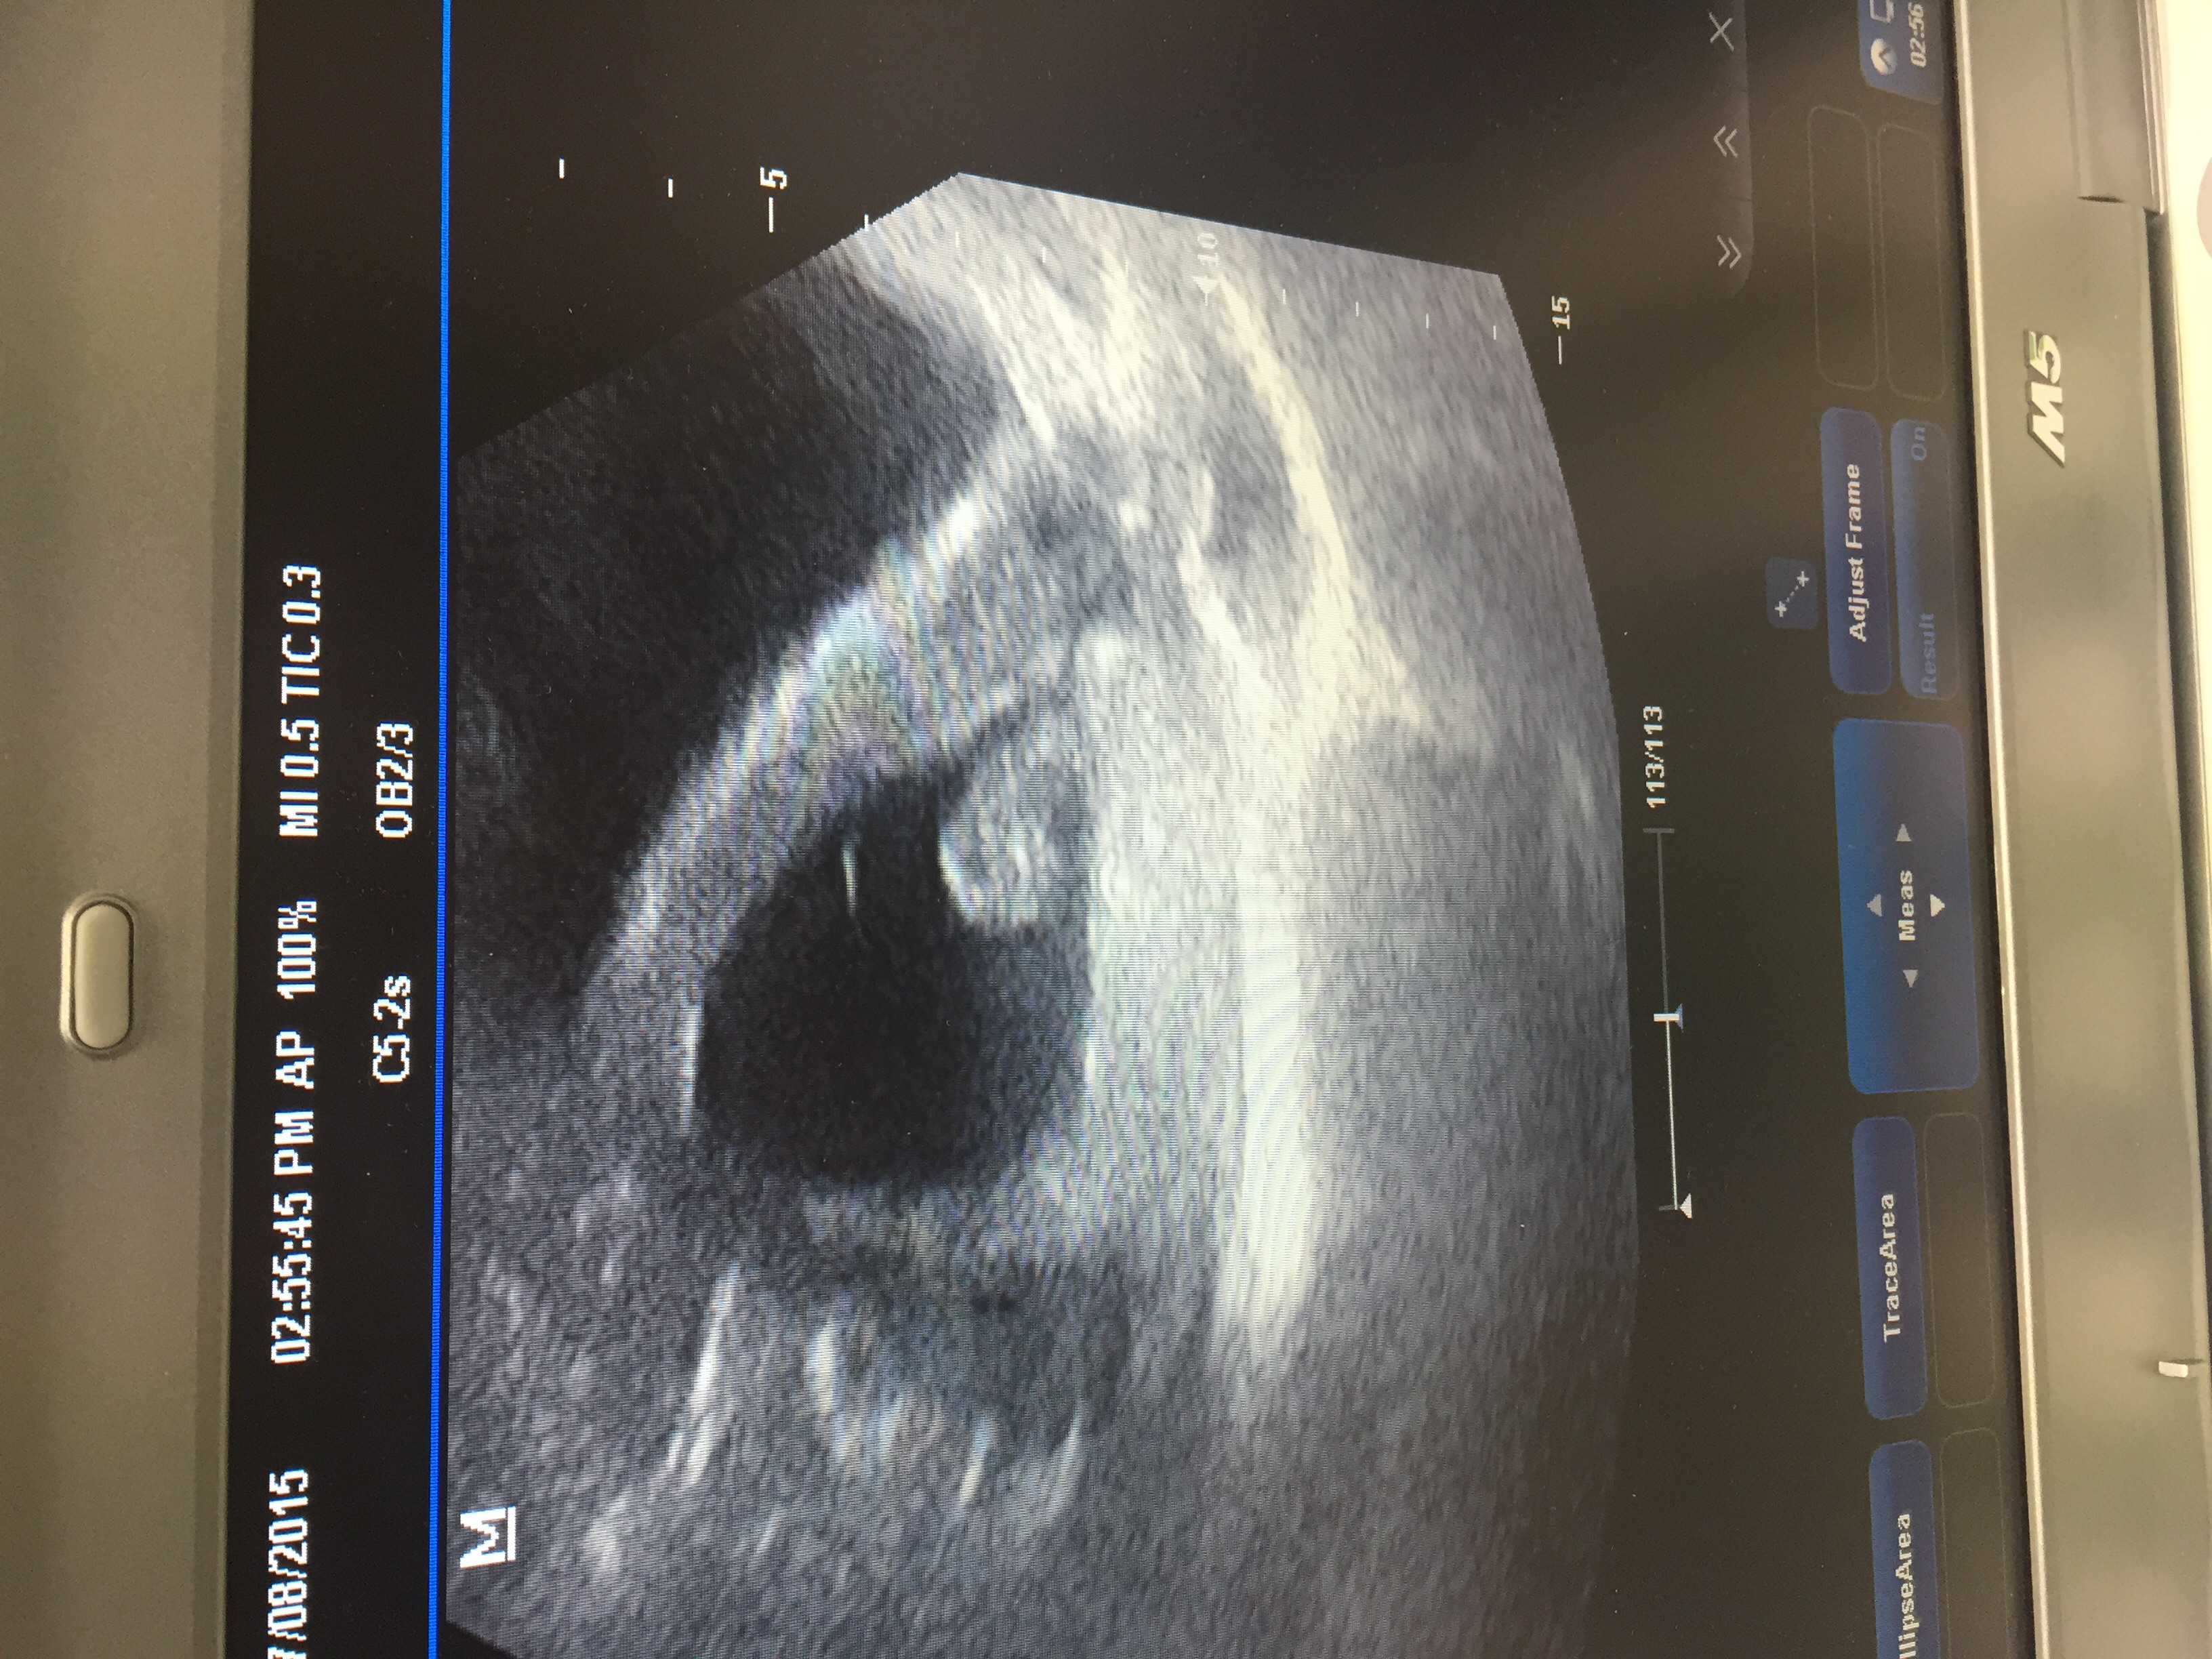

Is 9 weeks to late?? Scanned at 9 weeks 2 days should have been 8w6d Any guesses please?????Attachment 26925